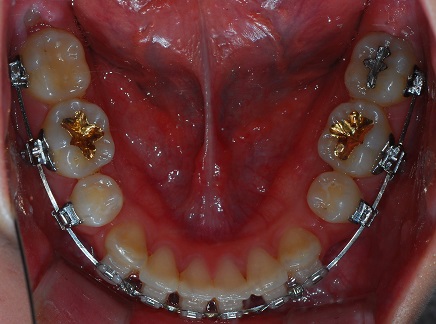

하악 사진

상악과 하악의 발치 공간의 차이가 좀 보이네요